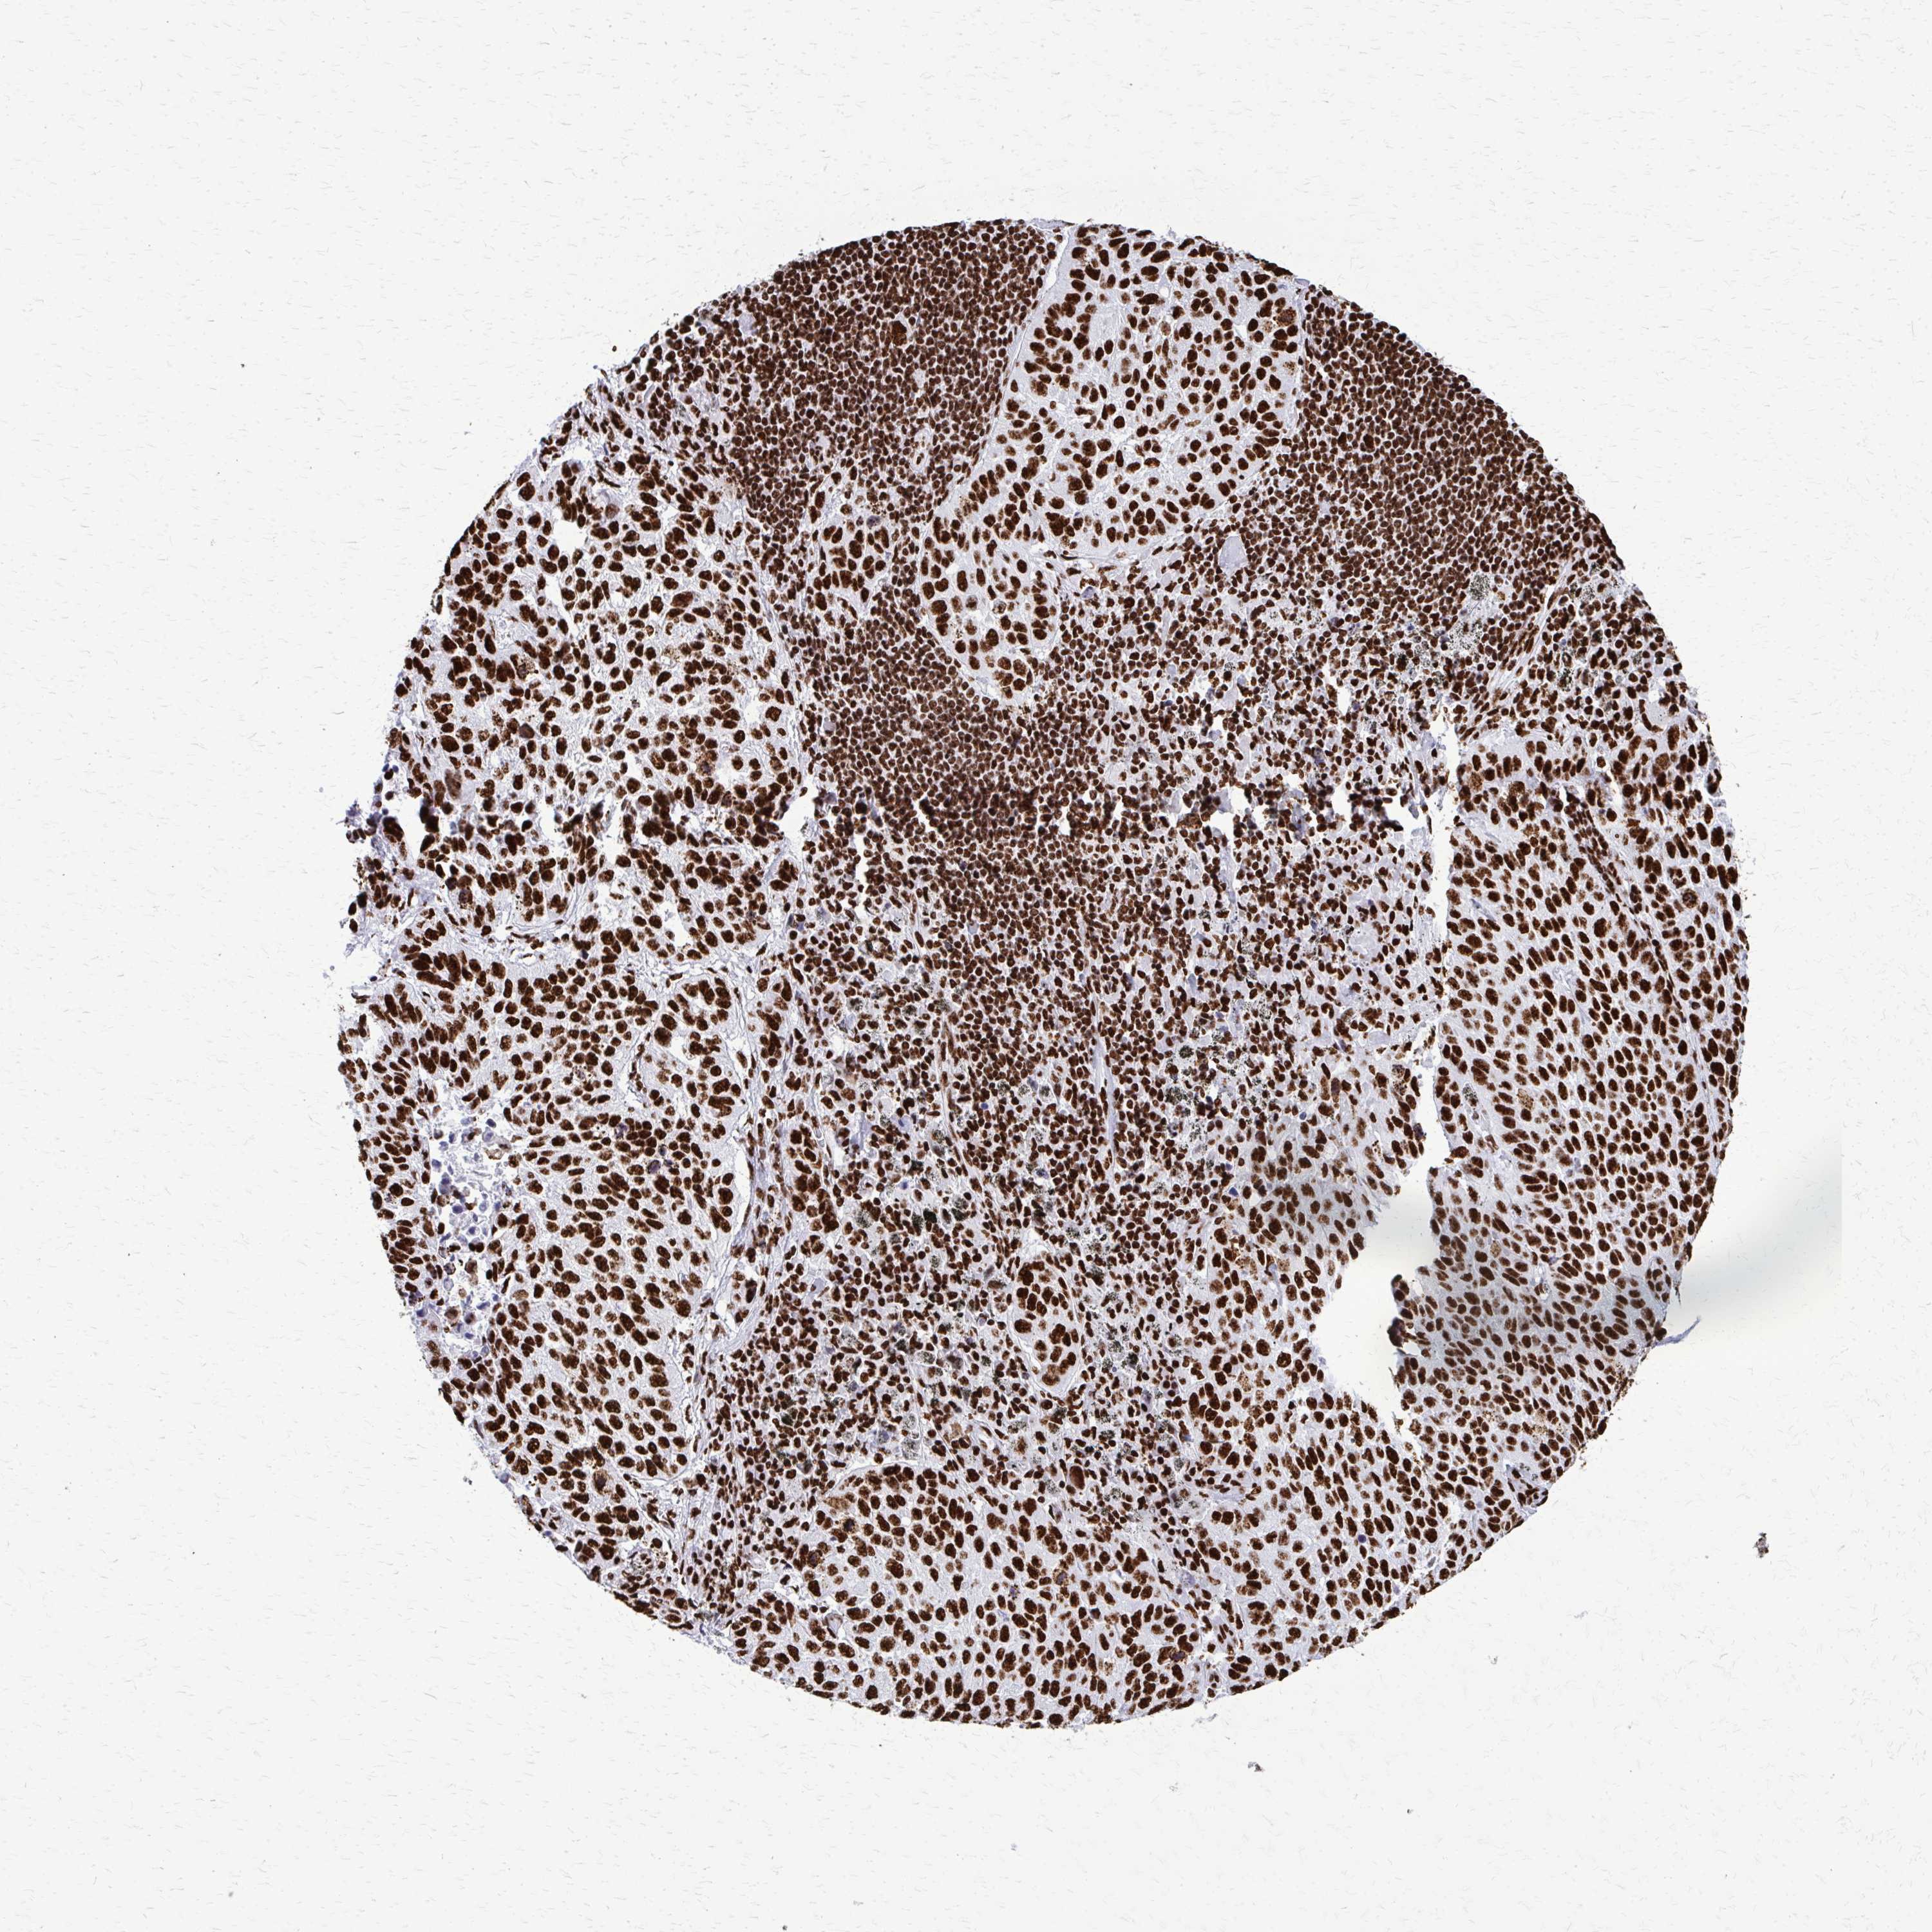

LUNG ADENOCARCINOMA (VALIDATION) - Interactive survival scatter ploti

SFPQ is not prognostic in Lung Adenocarcinoma (validation)

: 73.08

Average pTPM 83.1

Number of samples 105